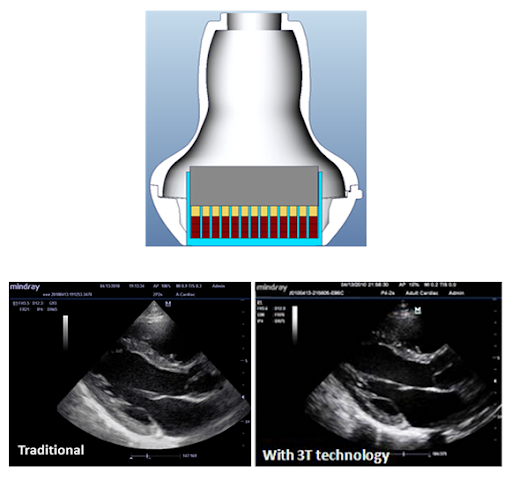

3T Технология производства датчиков

Запатентованная компанией Mindray технология датчиков, обеспечивающая расширение диапазона частот и повышение эффективности передачи изображений.

Тройная структура согласующего слоя обеспечивает повышенную чувствительность, более широкий диапазон частот и улучшенное соотношение «сигнал/шум»

Применение полностью разделенных кристаллов для снижения перекрестных помех, улучшения фокусировки и повышения поперечного разрешения

Терморегулирование для лучшей передачи звуковой волны